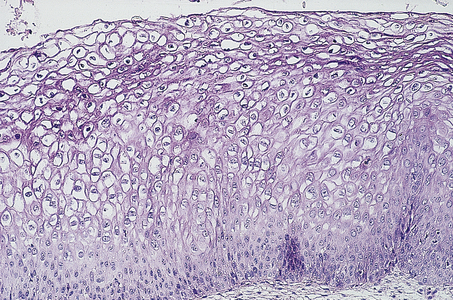

image

Fig. 19.8 Cervical intra-epithelial neoplasia (CIN) grade 3. Note that there is minimal surface differentiation.